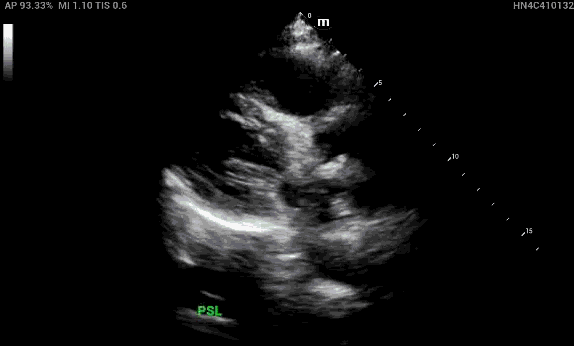

In the parasternal long view, the right ventricular outflow tract (RVOT), aortic root and left atrium should all be about equal in size (rule of thirds), however the RVOT looks enlarged in comparison.

In the parasternal short view, notice that the right ventricle is enlarged compared to the left ventricle. Also, there is bowing of of the interventricular septum during diastole, aka “D sign” — this is concerning for right heart strain.